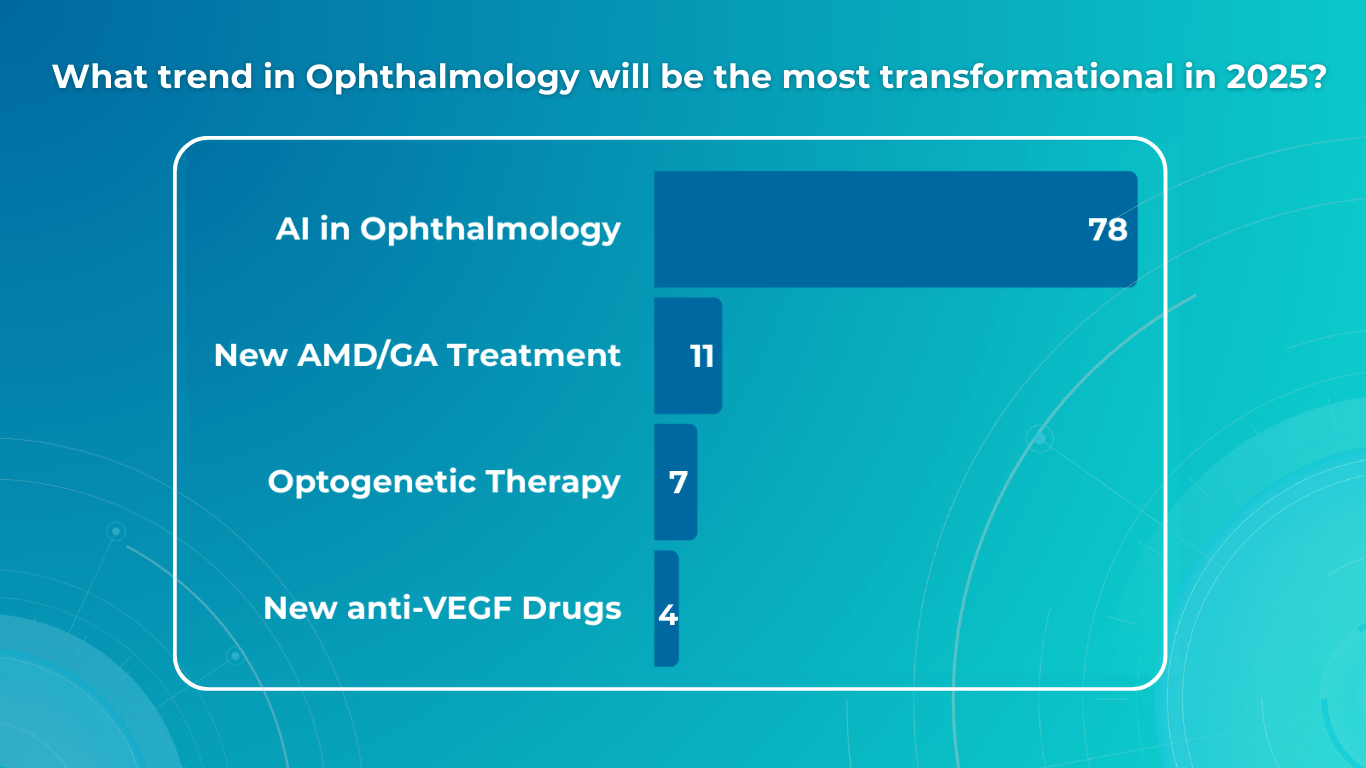

For this article, we surveyed eye care professionals on which optometry technology appears most promising to them. The answers were divided among AI for more precise diagnostics, advanced contact lenses, and new iterations of OCTs.

AI has blossomed in recent years, transforming not only how we work and relax but also how we manage our health. It’s no surprise that our survey of professionals revealed AI as the most promising technology in optometry.